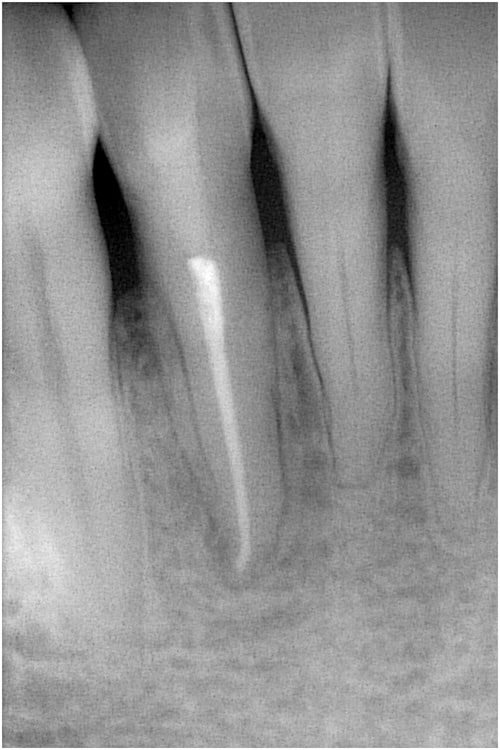

症例4 非外科 病変あり 前歯

治療前

症例4 非外科 病変あり 前歯 治療前

石灰化にて治療困難の為、紹介にて来院

治療途中

症例4 非外科 病変あり 前歯 治療途中

治療後

症例4 非外科 病変あり 前歯 治療後